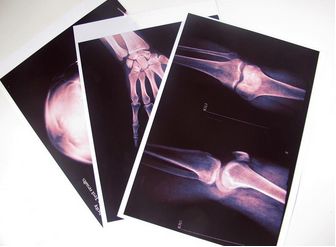

醫(yī)用X光膠片組成成份

醫(yī)用X光膠片里有一些很主要的成份,明膠就是是醫(yī)用X光膠片組成成份里不可或缺的。明膠是從動(dòng)物骨骼中提煉出來(lái)的膠性物質(zhì)。呈淡黃色。明膠的作用就是使鹵化銀晶體附著于

醫(yī)用X光膠片里有一些很主要的成份,明膠就是是醫(yī)用X光膠片組成成份里不可或缺的。明膠是從動(dòng)物骨骼中提煉出來(lái)的膠性物質(zhì)。呈淡黃色。明膠的作用就是使鹵化銀晶體附著于片基上,處于永 久性懸浮狀態(tài),而不互相接觸、堆積。

明膠能提高乳劑的感光度,與銀離子相互作用形成一種不穩(wěn) 定的鉻合物。吸收鹵原子。明膠還是一種保護(hù)性膠體,使銀鹽顆粒不互相接觸,保持結(jié)構(gòu)上的獨(dú)立。明膠膨脹后有多孔性,利于膠片制作和沖洗。

明膠具有熱熔冷凝的性質(zhì)。粘性強(qiáng)。明膠擁有堅(jiān)膜的作用。但卻有不穩(wěn)定性。

醫(yī)用X光膠片不含色素,所感受的是由X線激發(fā)下的藍(lán)紫色熒光,稱為色盲片。而感綠片和間接攝影用膠片則是在乳劑中加入色素,改變?nèi)閯┑奈辗逯祦?lái)提高感光度。

片基是膠片支持體,決定膠片的機(jī)械性能,纖維素酯片基分別有硝酸纖維素酯片基和三醋酸纖維素酯片基。硝酸纖維素片基,于1889年開始使用,特性是伸縮性及耐水性好,缺點(diǎn)是可自燃,在第 二次世界大戰(zhàn)中被醋酸纖維素代替。

醋酸纖維素乃基可分為二醋酸片基和三醋酸片基。特性是不易自燃,化學(xué)穩(wěn)定性較高。但缺點(diǎn)是質(zhì)地較脆,不耐寒、機(jī)械強(qiáng)度較差,顯影過(guò)程易產(chǎn)生收索現(xiàn)象。先多以聚酯片基為支持體,特別是自動(dòng)沖洗機(jī)。

干式激光醫(yī)用X光膠片的成像步奏一般分為5步:1、紅外激光掃描膠片并形成潛影;2、將曝光后的膠片用熱敏鼓加熱處理;3、將加熱溫度控制在1220C,時(shí)間控制在15秒;4、感光的鹵化銀受熱還原成銀原子,并在潛影中 心處堆積;當(dāng)潛影達(dá)到足夠數(shù)量后則構(gòu)成可見影響。